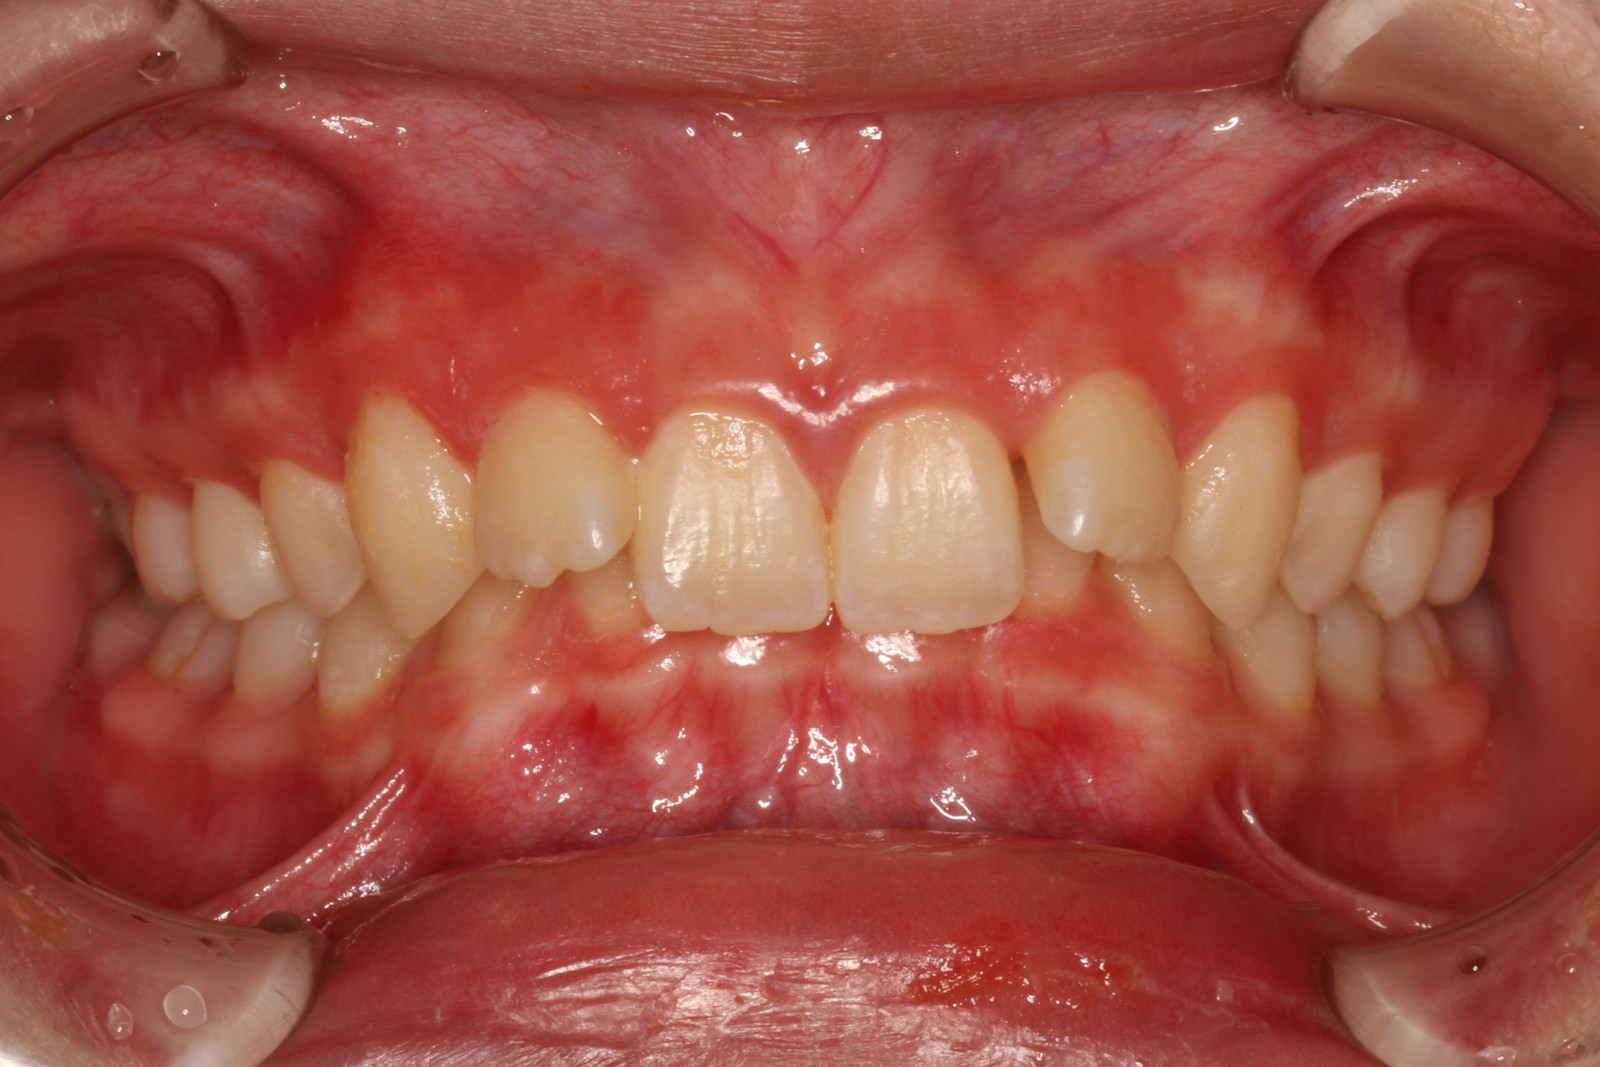

問診を行い、お口の悩みや希望を確認します。レントゲン撮影や口腔内写真の撮影など、必要に応じた精密検査を行います。